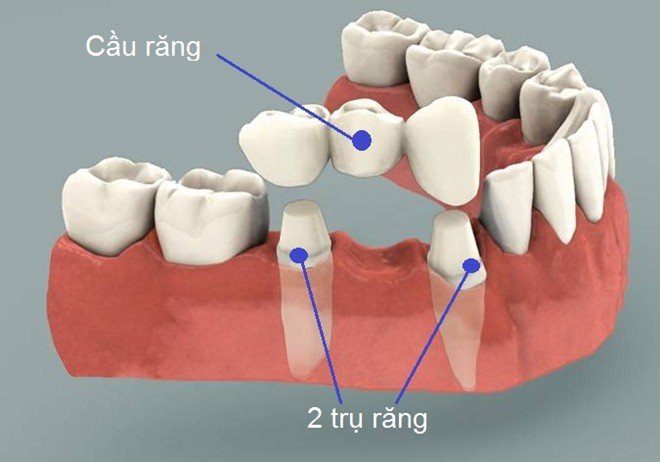

2.1 Cầu răng sứ là phương pháp thay thế một hay nhiều chiếc răng bị mất.

Ưu điểm:

- Chi phí điều trị rẻ hơn so với phương pháp Implant.

- Có tính thẩm mỹ tương đối cao.

- Thời gian phục hình ngắn và có thể được hoàn thành chỉ sau khoảng 3-4 lần hẹn gặp các bác sĩ chuyên khoa.

Nhược điểm:

- Bệnh nhân cần phải được tiến hành mài răng 2 bên nhằm gắn cầu răng sứ và điều này có thể khiến cho các răng này không còn được bảo tồn nguyên vẹn.

- Sau một thời gian thì bệnh nhân có thể sẽ gặp phải tình trạng tiêu xương.

Trong trường hợp bạn bị mất nhiều răng, việc làm và mang một phục hình tháo lắp bán phần khiến bạn cảm thấy rất phiền phức? Implant làm trụ nâng đỡ cầu răng, thay thế cho các răng đã mất sẽ giúp bạn tìm lại được sự vui thích khi ăn, nhai, cảm thấy tư tin trong khi cười, chúng có đầy đủ các chức năng và hình dáng bên ngoài y như các răng thật.